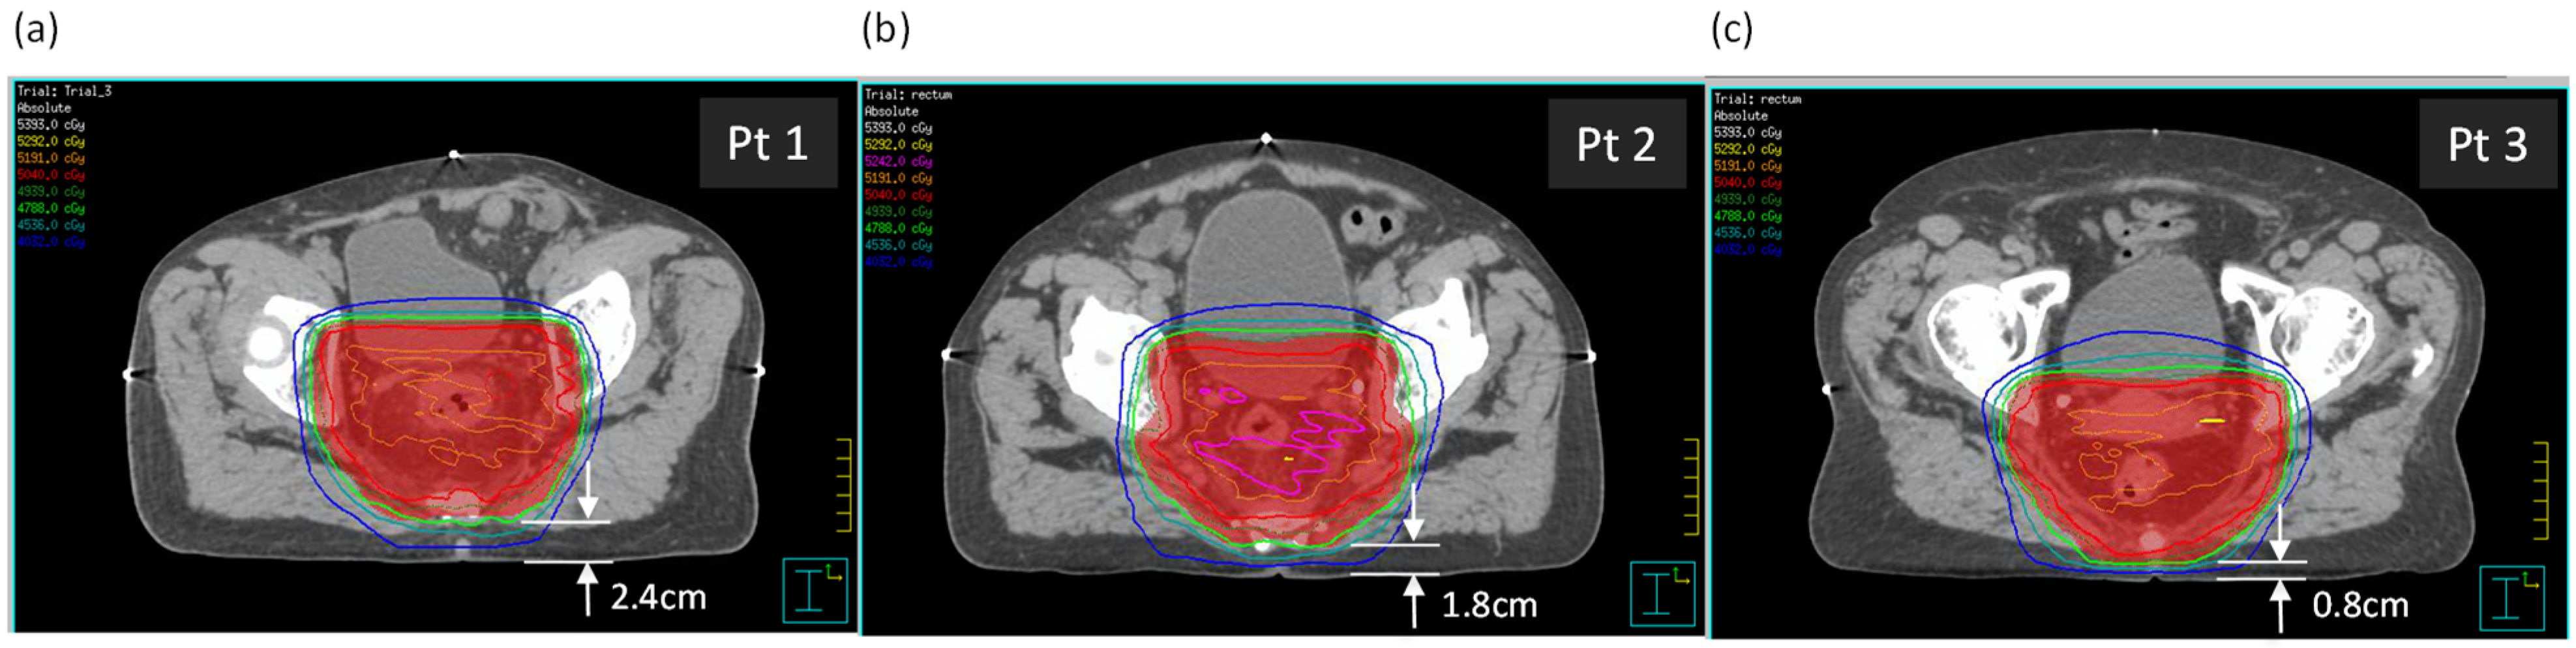

Three rectal cancer patient plans with supine setup were selected, with varying distances between the posterior skin surface and the planning target volume (PTV). Dimensions relevant to the study are in Table 1. The three patients were selected partially due to similar anterior–posterior (AP) and lateral separations, as well as a variation in the distance between the posterior surface and the PTV (see Figure 1). The tabletop height (TTH) is the distance from the posterior surface to the treatment isocenter.

Figure 1.

The three patients, (a) Patient 1, (b) Patient 2, and (c) Patient 3, shown at the axial isocentric plane. Distances from the posterior surface to the PTV are shown.